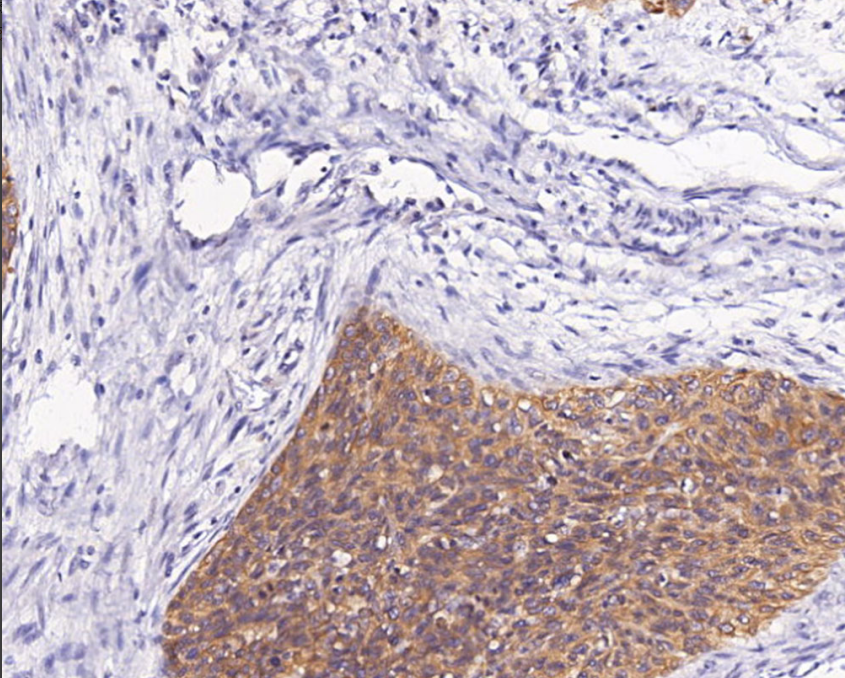

细胞定位:细胞质/膜

阳性对照: 食管鳞状细胞癌/喉鳞癌/口腔鳞癌

CK4为II型细胞角蛋白,和CK13一起在黏膜和食管上皮组织中特异表达。CK4编码基因突变与粘膜白色海绵状痣有关,表现为口腔、食管和肛门黏膜白斑病。

CK4抗体试剂可与CK4分子抗原特异性结合,含CK4抗体试剂的免疫组化试剂盒适用于食管鳞癌、头颈鳞癌等的辅助诊断。